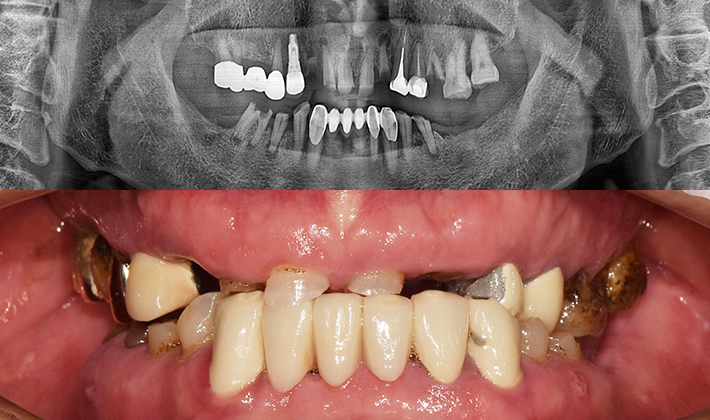

치과가 무서워 10년 동안 미뤄온 임플란트 수술 그 결과는?

2026.01.21